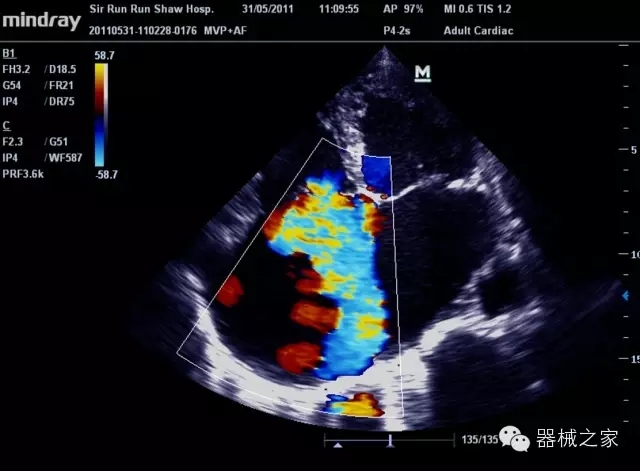

經(jīng)典產(chǎn)品:M7(星鉆)

臨床圖片賞析

產(chǎn)品特點(diǎn)

·裝載有采用Multi-Core多核處理的非嵌入式平臺(tái),成像效率大大提高,并且能夠給用戶帶來高速、多任務(wù)并行信號(hào)處理體驗(yàn);

·優(yōu)秀的圖像效果、強(qiáng)大的功能體驗(yàn)、豐富的探頭選擇、合理的便攜式設(shè)計(jì),全中文顯示及病人管理界面,使得M7在任何場合、任何時(shí)候都能快速響應(yīng)更好的心血管、腹部、婦產(chǎn)、小器官等常規(guī)超聲檢查以及肌骨、神經(jīng)、顱腦、術(shù)中等新興領(lǐng)域的使用需求;

8倍波束并行處理系統(tǒng)

·在便攜式緊湊平臺(tái)上采用更多倍波束并行接收信號(hào)處理模式,無論二維還是彩色血流圖像狀態(tài)下,擁有更靈敏的回波頻移捕獲能力,大大提高時(shí)間分辨率,尤其使得心血管表現(xiàn)更為突出;